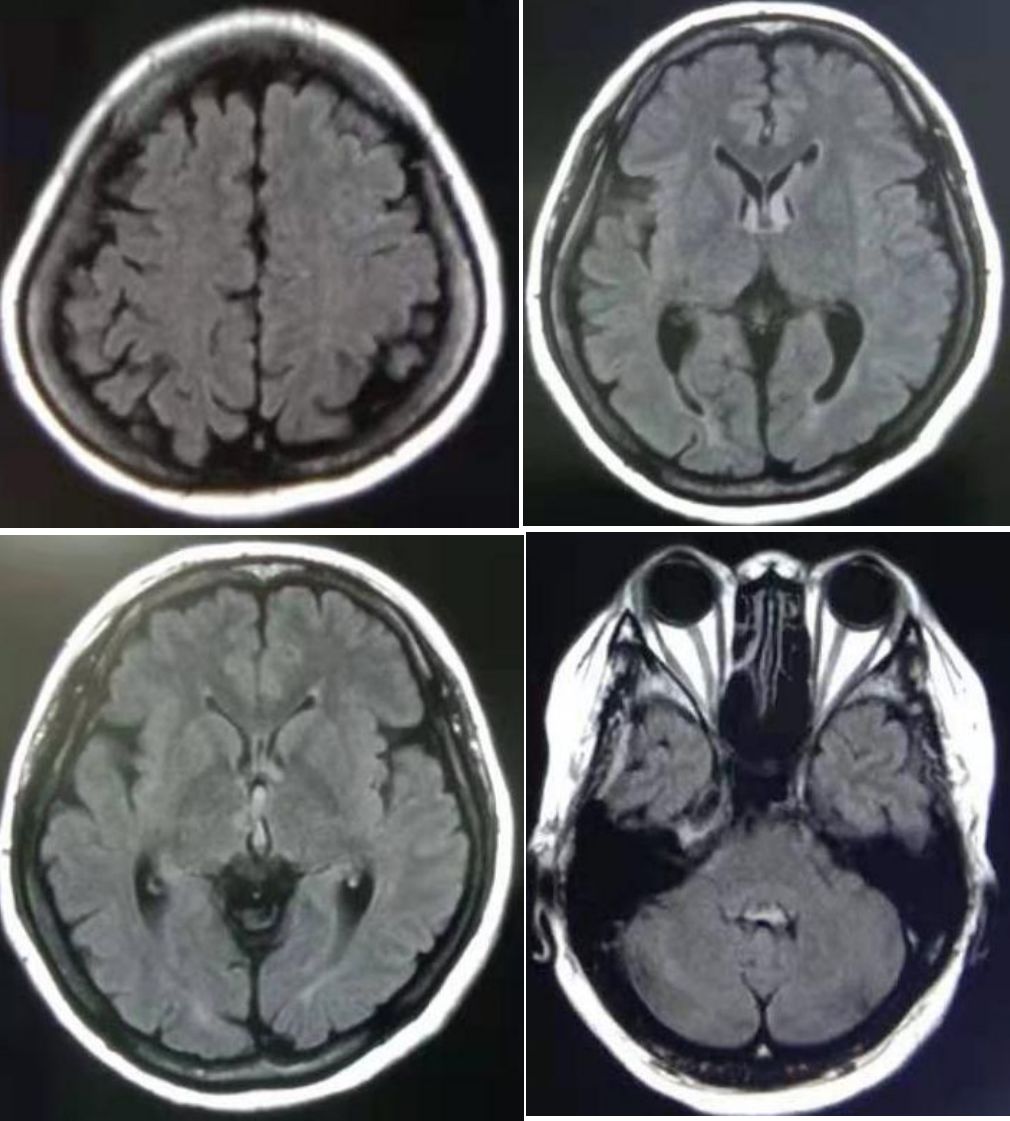

病例6

28岁,女性,口唇颜面麻木。头MRI如下:

激素冲击5天后减轻,次年复查MRI见下图,病灶外形、大小等特点无变化。

答案:颅内毛细血管扩张症(Intracranial capillary telangiectasia,ICT)。

ICT是胚胎时期毛细血管胚芽发育异常而形成的畸形血管团,显微镜下表现为一堆扭曲、扩张的薄壁微血管。一般无症状,通常是在现的一种血管畸形,常见于脑桥基底部和小脑,不需要治疗。诊断要点:

➤ T2WI、FLAIR序列点状或结节状高信号。

➤ 由于缓慢流动的血液中存在脱氧血红蛋白,在GRE上呈低信号。

➤ 呈“毛刷状”或“点状”增强。

➤ DSA多无阳性发现。

需要和动静脉畸形、静脉性血管畸形、海绵状血管瘤、肿瘤转移、创伤等鉴别。